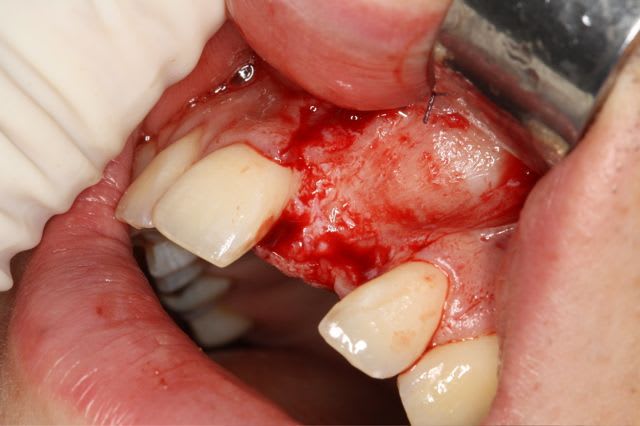

Pour le fun ! car pas bcp de photos en ce moment sur nonol

la dent était absente depuis 8 ans suite à "accident" de la vie (à 5h du mat'...)

très classiquement:

greffe onaly,

dépose des vis et pose de l'implant à 5mois1/2 avec un cj roulé et mise en place de la vis de cica,

et 3 mois 1/2 après empreinte

15j après essayage pilier et biscuit, visite au labo pour "finition en bouche" et 3 h après scellement.

en temporisation, la vieille PAP du patient (raison €€€ )

pour la greffe: un lit de copeaux généreux et un bloc corticale par dessus et des copeaux pour boucher les espaces. Pas de membrane par dessus, seulement le périoste.